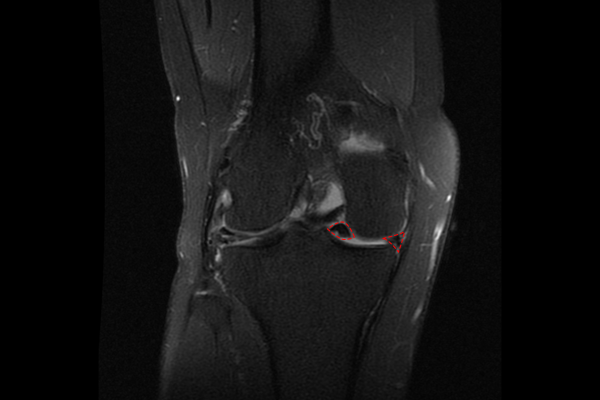

촬영된 MRI 사진을 보았을 때 반월상 연골판이 양동이 손잡이형 파열(bucket-handle tear)된 것이 확인됩니다. 정면 MRI를 보시면 반월상 연골이 2개로 갈라져서 반은 앞으로 튀어나오고 반은 안쪽에 들어가 있는 나비넥타이 모양이 확인됩니다.